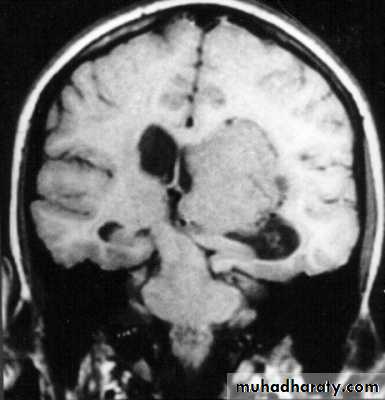

Chronic Subdural Haematoma

Most common in infants and in adults over 60 years of age secondary to SLIGHT blow to the head which may pass unnoticed.

Source of bleeding (haematoma): usually from bridging veins as they pass to the venous sinuses.

The patients present with progressive neurological deficits more than 3 weeks after the trauma.

The initial head injury is often completely forgotten.

CT scan: the acute clotted blood is initially appears white (hyperdence), but as it liquefies, it slowly becomes black (hypodense).

They should be drained if they continue to enlarge.

They are evacuated by drilling burrholes over the collection and washing it out with warmed saline.